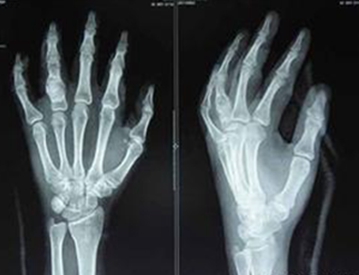

患者姓名:周老师 年龄:45岁 病种:风湿性关节炎 病史:8年

HD-热层析检测:腕关节炎性介质明显,且有加重、增多趋势,腕关节痛重,累及关节往肘关节发展。

检查数据:抗链球菌溶血素O(ASO) 284.8 u/ml,类风湿因子O(RF) 16.35 IU/ml,血沉(ESR) 31.6 mm/h。

(图:周老师手部CT图)

治疗后检查数据:

抗链球菌溶血素O(ASO) 35.7 u/ml;类风湿因子O(RF) 6.15 IU/ml;血沉(ESR) 6.38 mm/h。